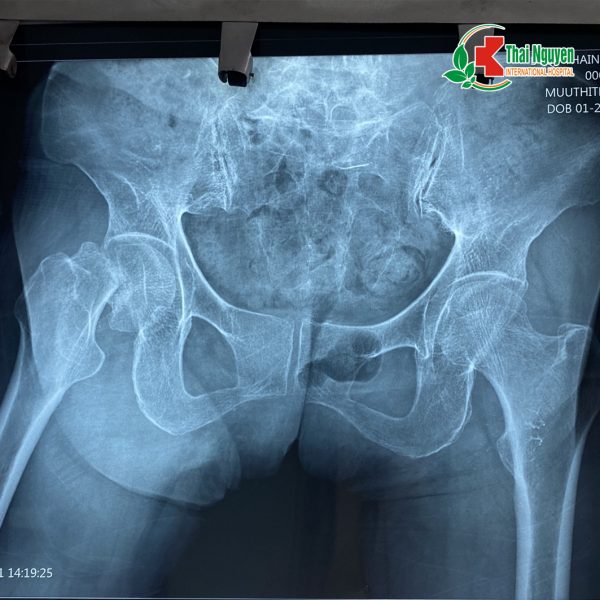

? Cụ bà Mưu Thị T, 76 tuổi, địa chỉ tại xã Cao Ngạn, thành phố Thái Nguyên, khoảng 2 tuần trước cụ bị ngã dẫn tới mất vận động chân phải, đi lại khó khăn. Gia đình đã đưa cụ tới khám tại Bệnh viện Quốc tế Thái Nguyên, kết quả chụp X-quang cho thấy cụ T bị gãy cổ xương đùi phải, có di lệch, được chỉ định phẫu thuật thay khớp háng bán phần bên phải.

Hình ảnh chụp Xquang của cụ bà Mưu Thị T thấy rõ vết gãy cổ xương đùi bên phải